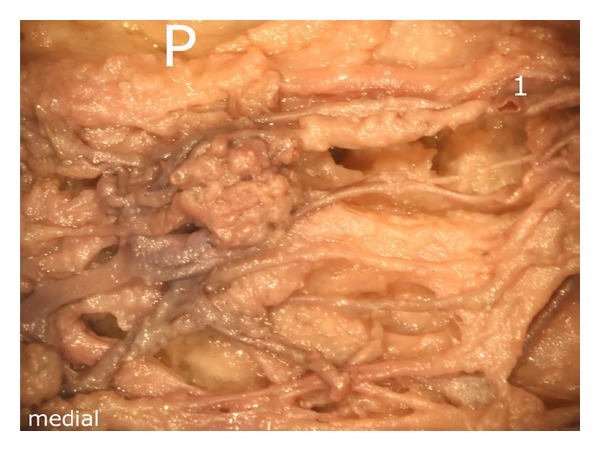

Even though the vascular supply of the human patella has been object of numerous studies until now, none of them has described in detail the rich arterial supply provided via the infrapatellar fat pad (of Hoffa). Therefore, we aimed to complete the knowledge about this interesting and clinically relevant topic. Five human patellae taken from voluntary body donators were studied at the Department of Applied Anatomy of the Medical University of Vienna. One was dissected under the operation microscope, a second was made translucent by Sihlers-solution, and three underwent angiography using a 3D X-ray unit. The results revealed that the patella to a considerable amount is supplied by arteries coursing through the surrounding parts of the infrapatellar fat pad. The latter were found to branch off from the medial and lateral superior and inferior genicular arteries. Within the infrapatellar fat pad, these arteries formed a dense network of anastomoses which are all contributing to the viability of the patellar bone. Due to the rich arterial supply reaching the patella via the infrapatellar fat pad, it seems advisable to preserve the fat pad during surgery of the knee in order to reduce the risk of vascular impairment of the patella.